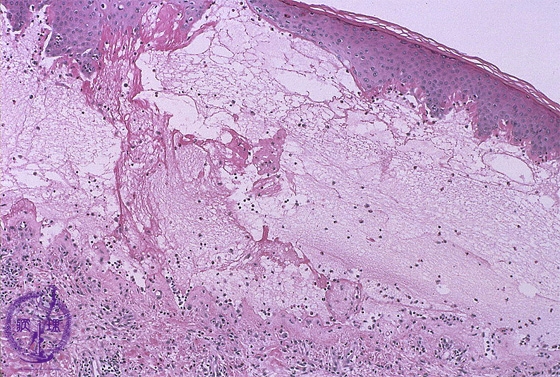

- ★(2)Vesiculobullous disease (Pemphigus vulgaris)

Microscopic image (Bullous pemphigoid): Fibrin deposition and numerous eosinophils are seen in the blister cavity. Eosinophil infiltration is also seen in the superficial dermis.